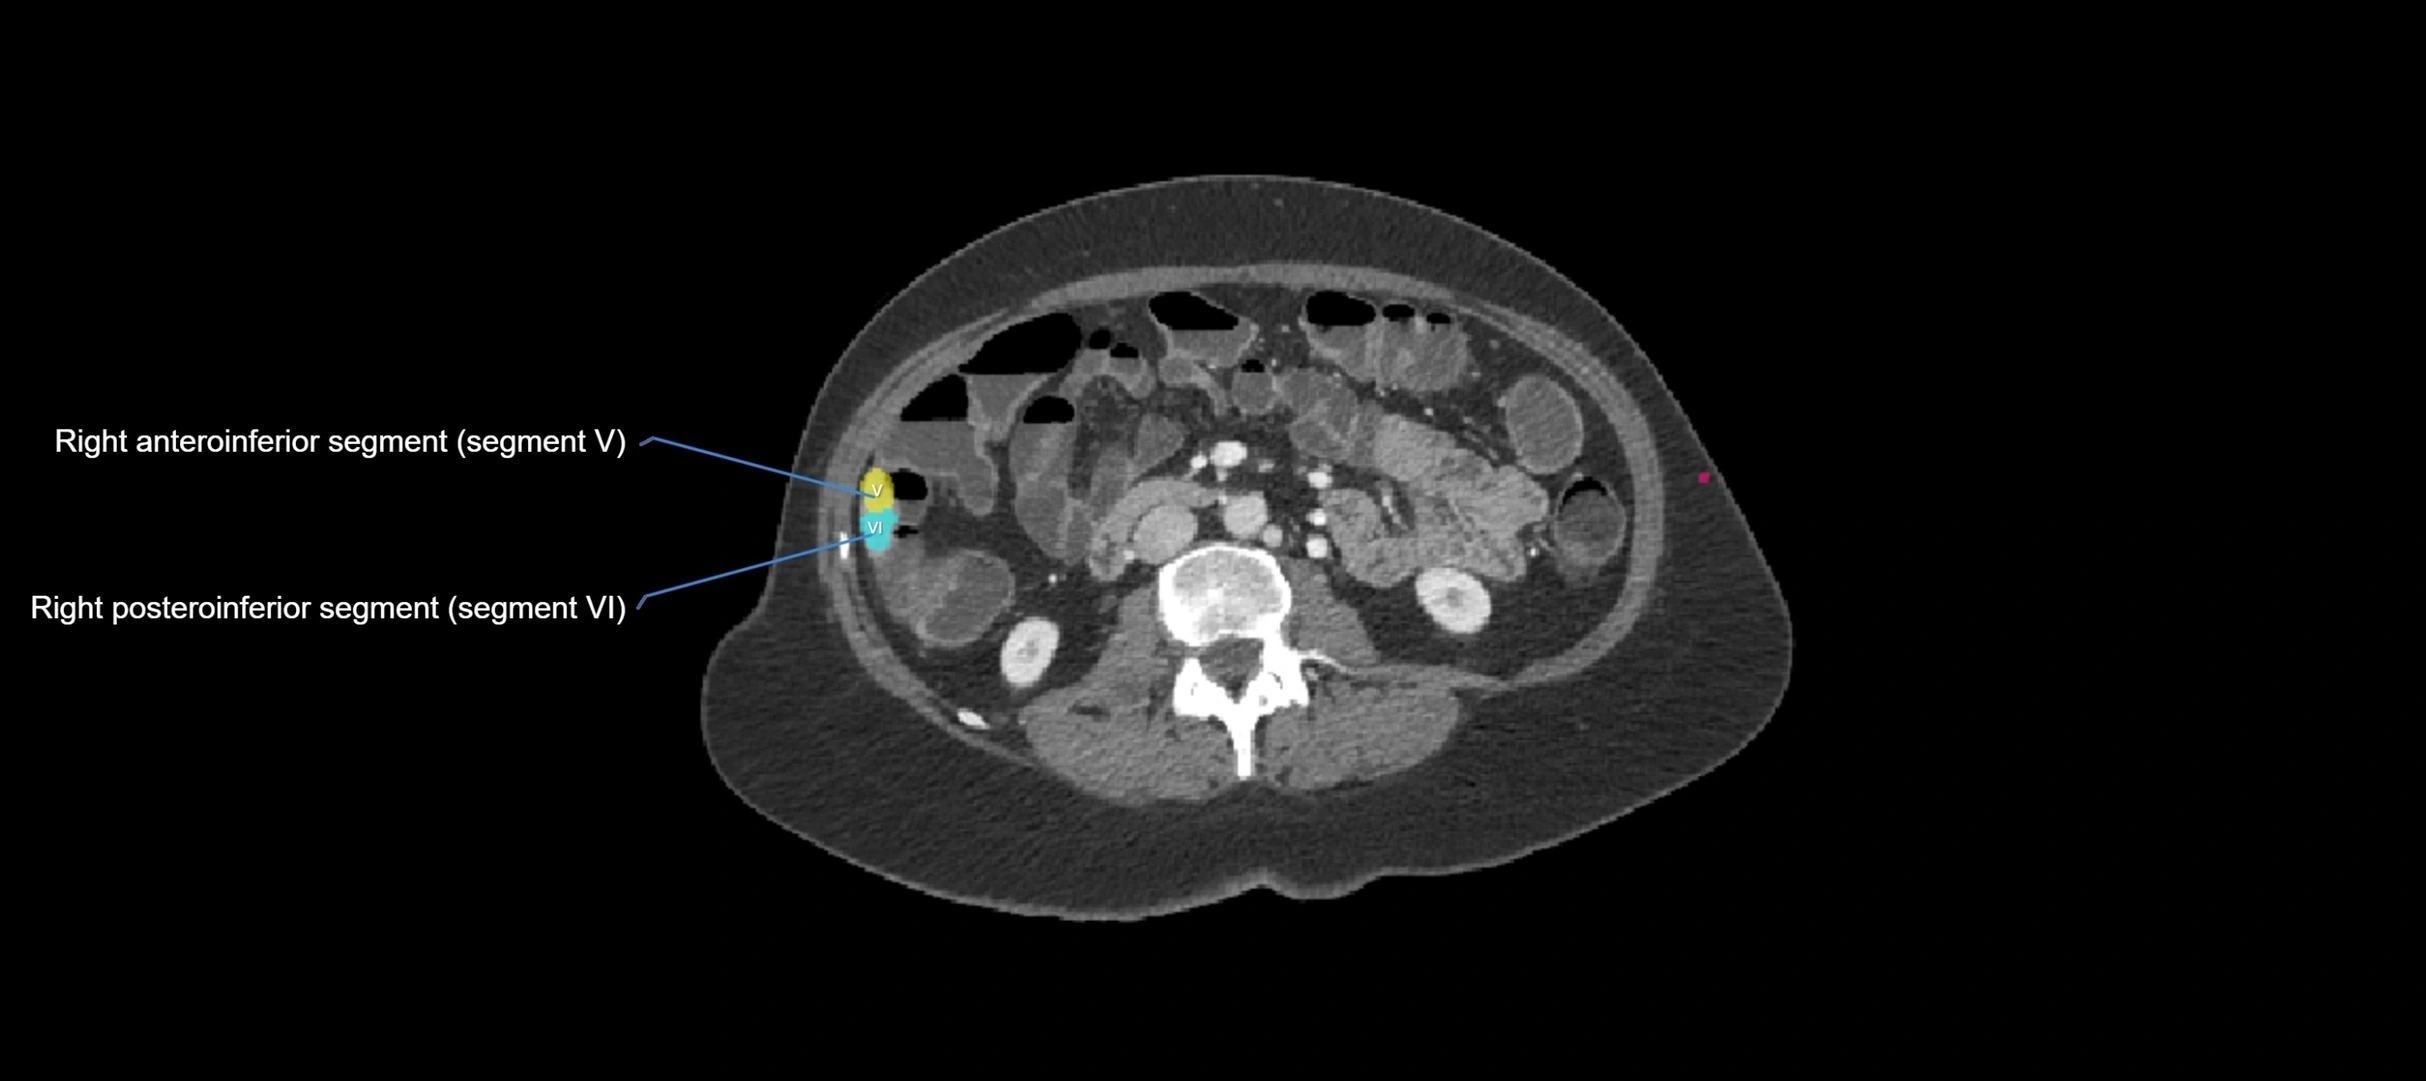

The caudate lobe of the liver is a distinct anatomical subdivision of the liver, designated as segment I in Couinaud’s classification. It lies on the posterior surface of the liver, between the fissure for the ligamentum venosum (left boundary) and the groove for the inferior vena cava (IVC) (right boundary). Superiorly, it is related to the posterior liver surface, and inferiorly it is separated from the left lobe by the porta hepatis.

The caudate lobe is unique because it receives dual portal venous and arterial inflow from both the right and left portal veins and hepatic arteries. It also has independent venous drainage directly into the IVC via multiple small hepatic veins, unlike other lobes that drain through the three main hepatic veins.

This anatomical autonomy makes the caudate lobe especially significant in liver surgery, transplantation, and hepatic venous outflow obstruction syndromes (e.g., Budd–Chiari syndrome). Enlargement of the caudate lobe is a characteristic imaging feature in chronic liver disease and cirrhosis.

CT Appearance

CT Pre-Contrast:

• Caudate lobe appears as a soft-tissue density, isodense to the rest of the liver

• Enlargement may be appreciated in cirrhosis or Budd–Chiari syndrome

CT Post-Contrast:

• Homogeneous enhancement in the portal venous phase, similar to rest of liver

• Independent venous drainage into the IVC may be visualized

• Lesions follow characteristic CT enhancement patterns (HCC: arterial hyperenhancement with washout; hemangiomas: peripheral nodular enhancement with centripetal fill-in)

CT Venous Phase (functional significance):

• Caudate lobe often enhances relatively more than other lobes in Budd–Chiari syndrome, due to preserved venous outflow